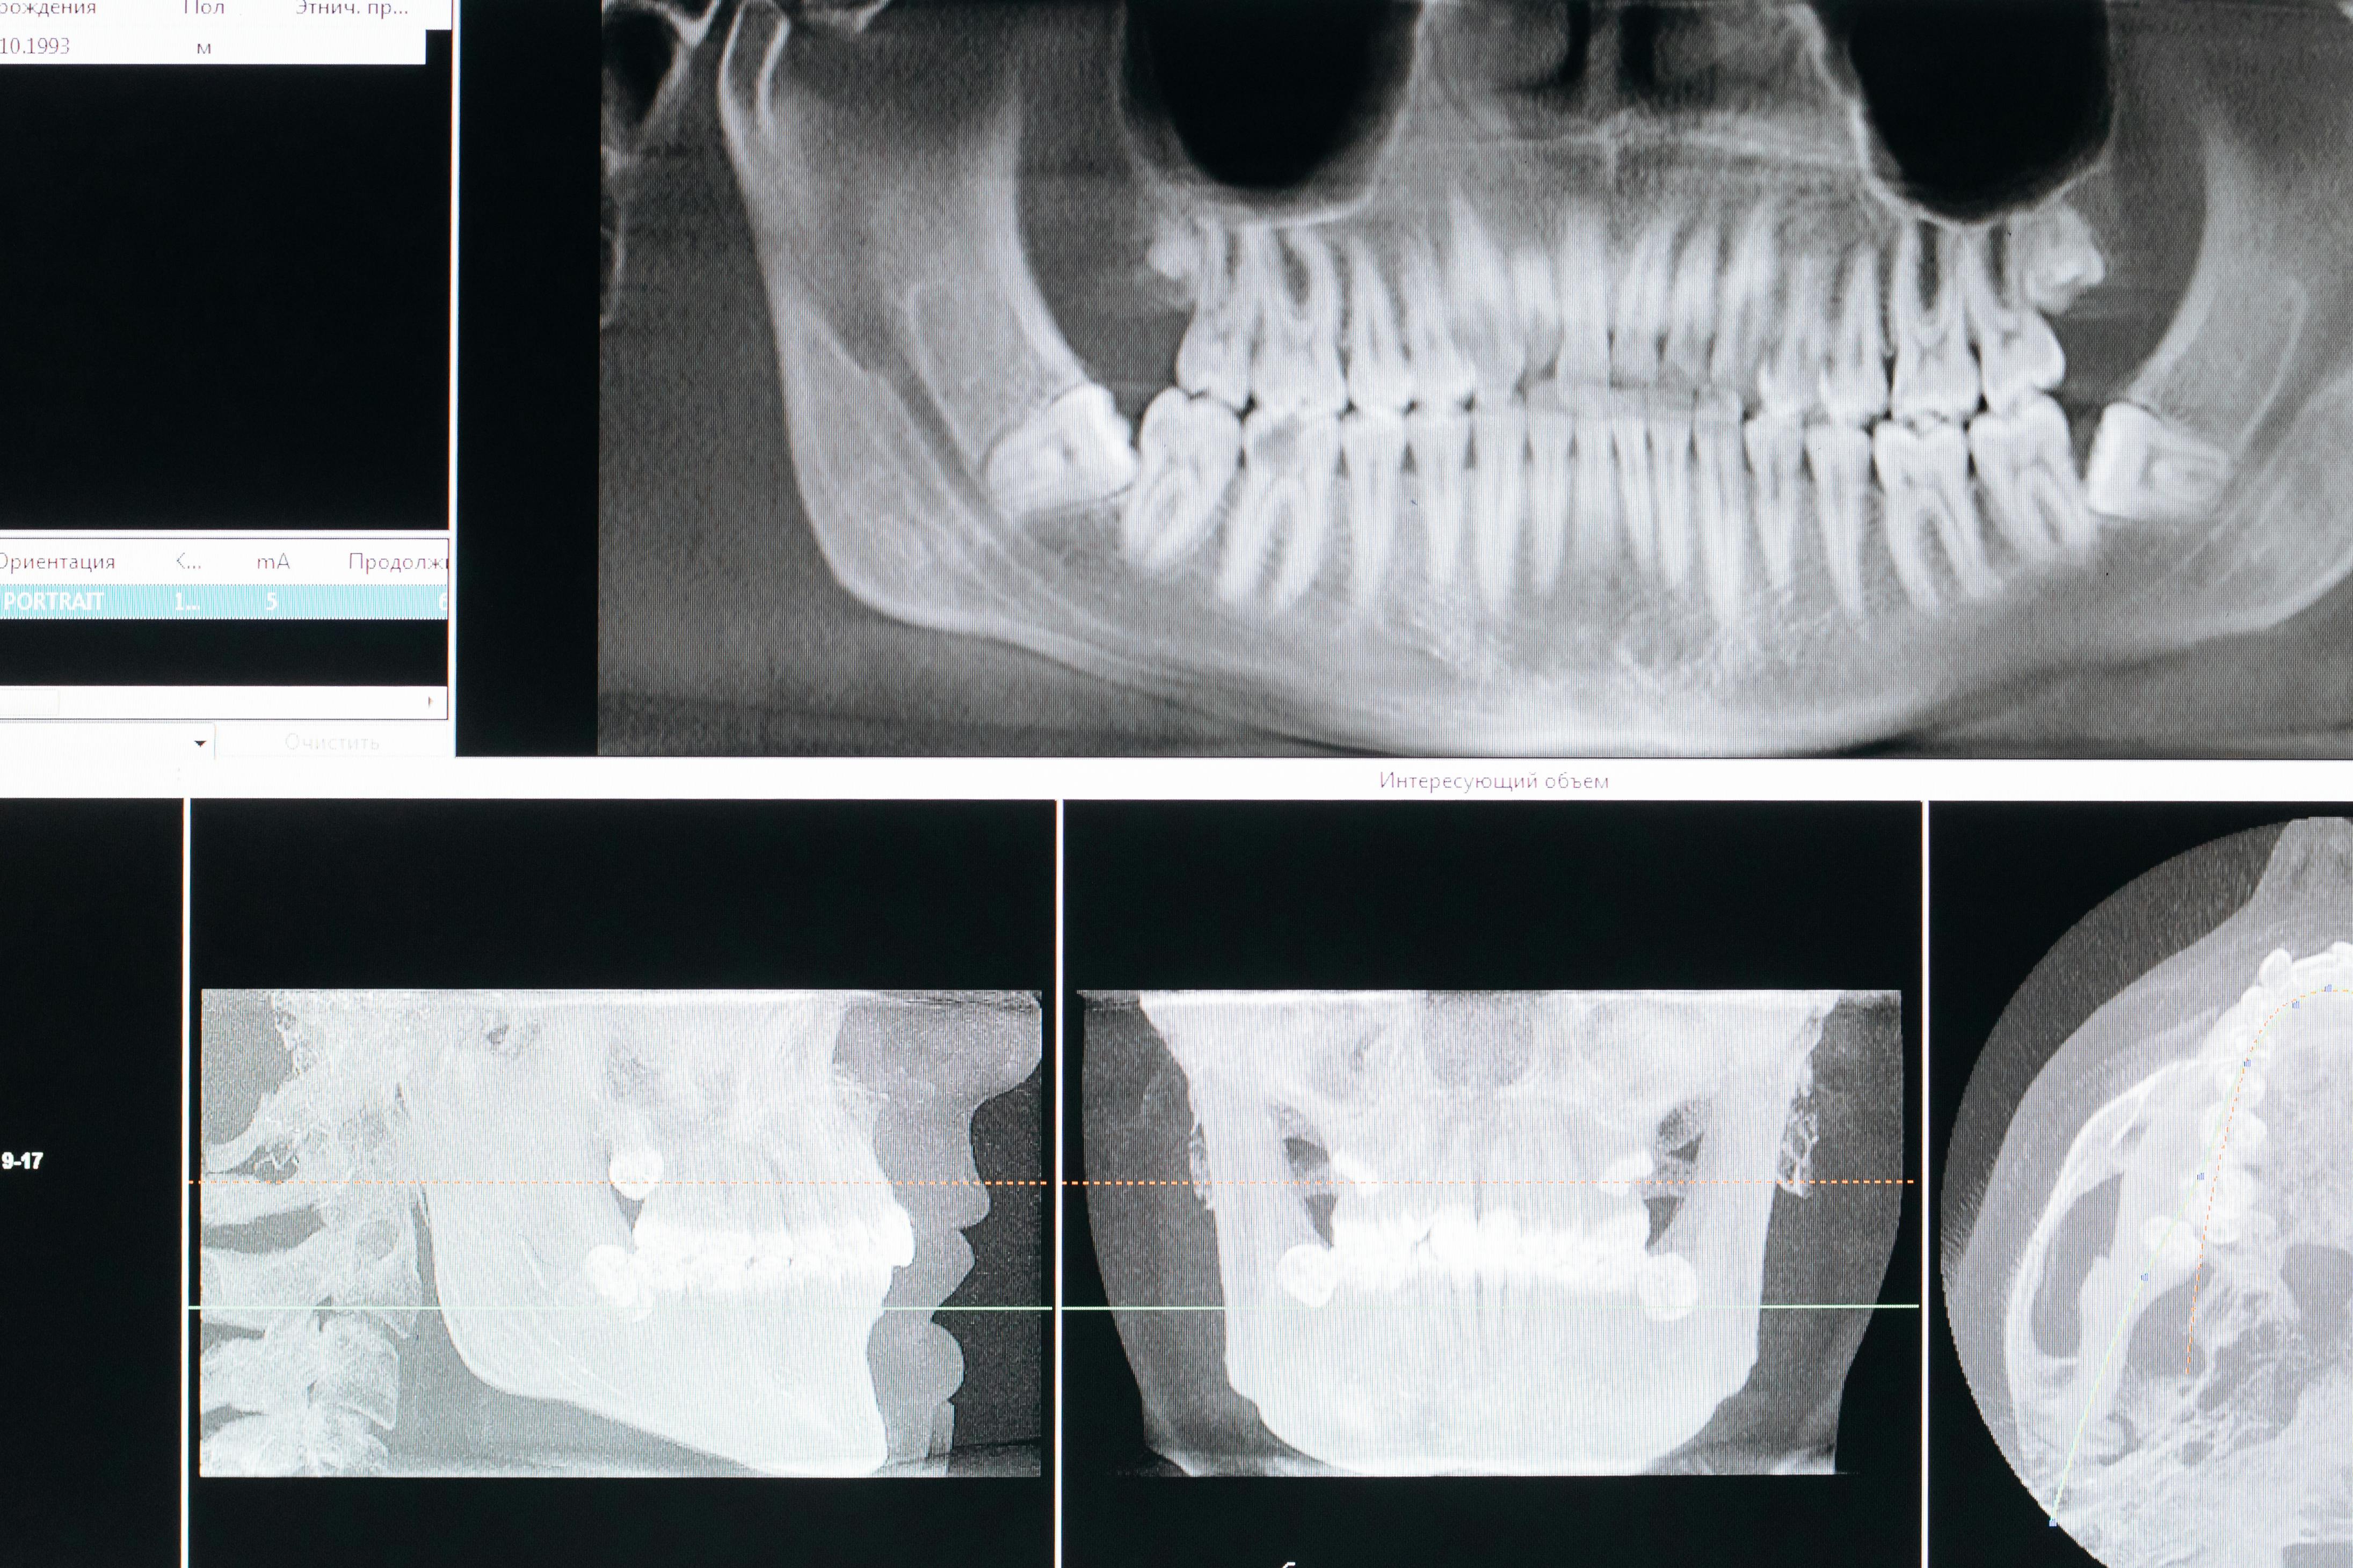

Radiografiile în ortodonție: tipuri, importanță și siguranță. De ce sunt necesare radiografiile pentru planificarea tratamentului.